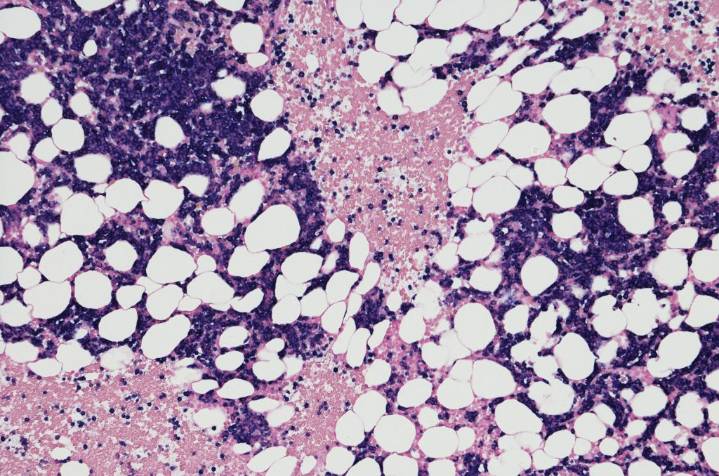

Researchers at the Icahn School of Medicine at Mount Sinai have identified specific features of the immune system help explain why some patients with multiple myeloma (MM) experience long-term remission following CAR T cell therapy, while others relapse within a few years. The research, published in Blood Advances , focused on the BCMA-targeted therapy cilta-cel and found that long-term MM survival was linked to an interaction between the infused CAR T cells and a patient’s own immune system.